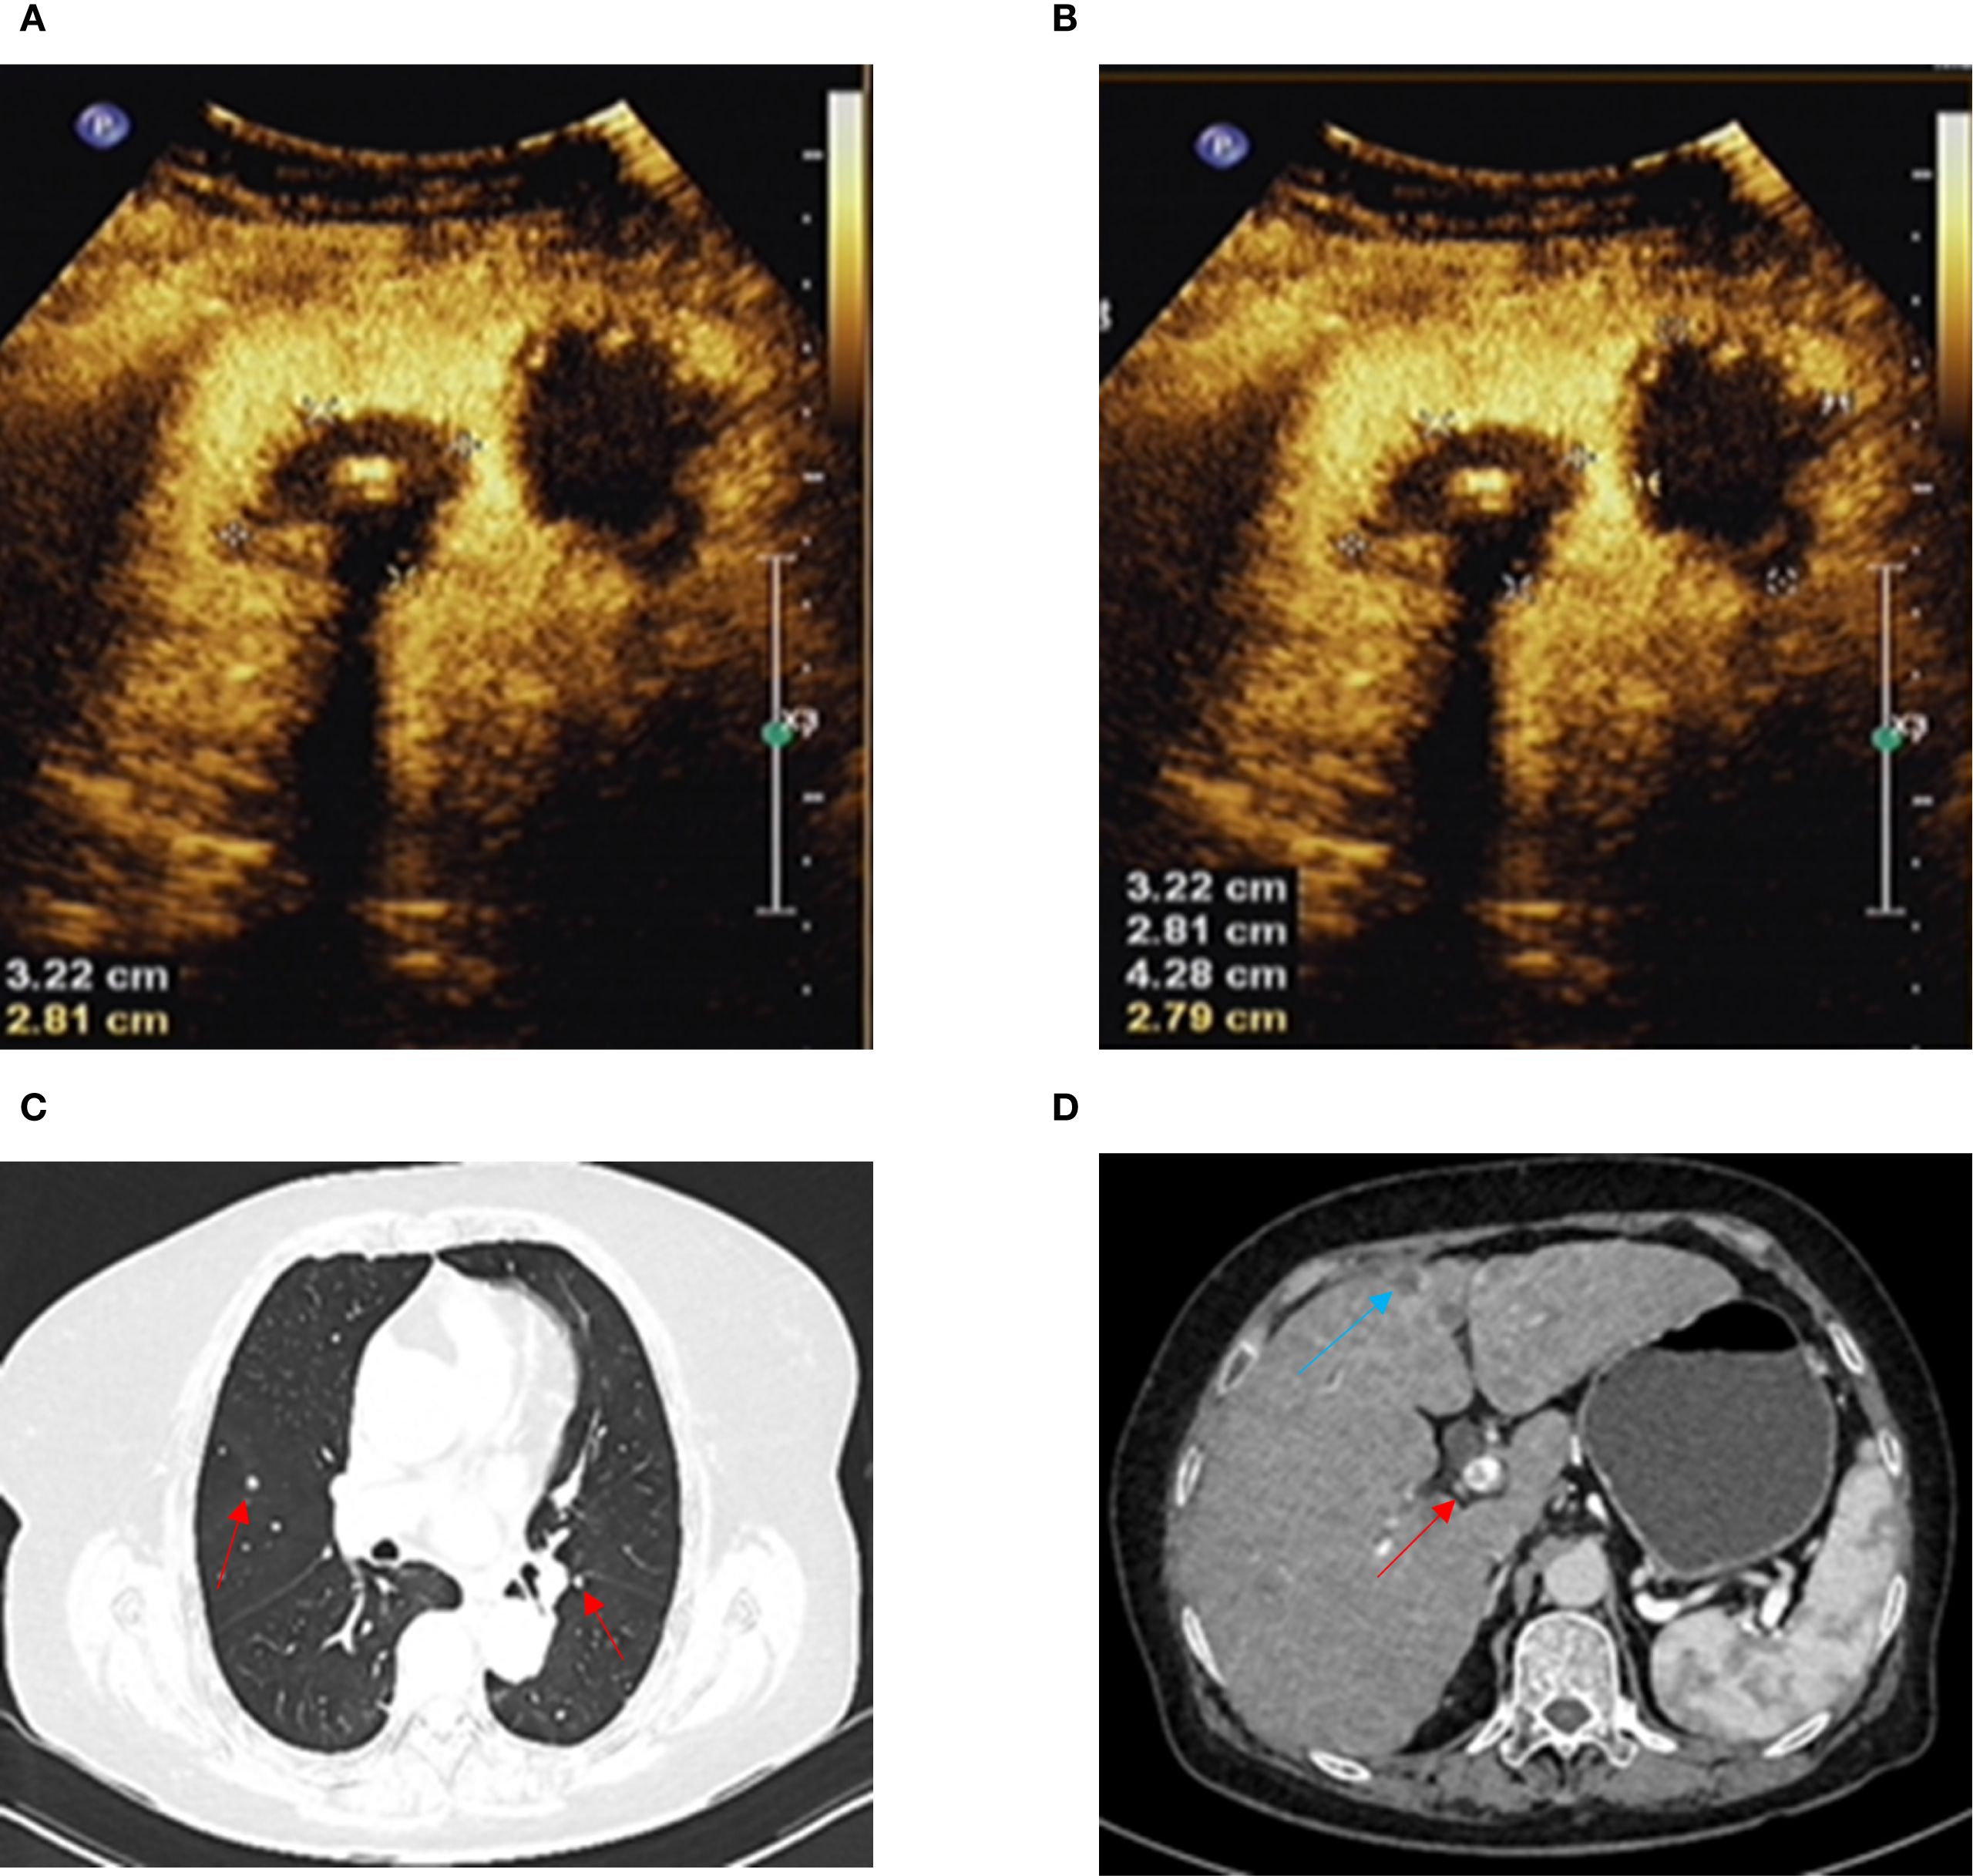

A 66-year-old woman with a complaint of intermittent anorectal bleeding and pain for 1 month. During this period, she underwent a colonoscopy at a local hospital, which revealed the presence of a rectal tumor. Due to limited medical conditions in local hospitals, surgical treatment was not performed. Subsequently, she presented to our hospital. The patient has no history of harmful habits or significant past medical conditions, and there is no relevant family history of genetic disorders. Physical examination revealed a non-tender mass measuring 4 × 3 centimeters in the anorectal region, located approximately 4 cm from the anal margin. Colonoscopy showed a rectal lesion of about 4 cm × 3 cm × 3 cm, located within 5cm of the anal verge, with visual erosion and hemorrhage (Figure 1A). Biopsy was taken for the final diagnosis. Rectal magnetic resonance imaging (MRI) showed a soft tissue mass protruding from the rectal wall, with no local lymph node enlargement (Figure 1B). Enhanced computed tomography (CT) of the chest and abdomen detected an occupying lesion protruding from the rectal wall into the intestinal lumen, as well as a circular low-density shadow in the 4/8 liver segment along with mild enhancement. No lymph node enlargement was found in the local area. (Figure 1C). Hematological examinations, in review including blood count, biochemical tests, carcinoembryonic antigen, and alpha-fetoprotein levels, were within normal ranges, except that CA 199 was 29.70U/ml. Histological biopsy findings (HE staining) showed that the tumor was composed of spindle-shaped and oval-shaped cells, exhibiting significant cellular atypia and nuclear division. Immunohistochemical staining revealed positive results for HMB 45. Expression of S-100 was negative. The expression level of Ki67 was 40%. Based on the histopathological cell morphology, immunohistochemistry, and imaging examination, the patient was preliminarily diagnosed with a primary AMM with liver metastasis. After obtaining written informed consent. The patient underwent transanal local resection for primary AMM and ultrasound-guided radiofrequency ablation for liver metastases. Postoperative contrast-enhanced ultrasound demonstrated complete inactivation of the liver metastases (Figures 2A, B). The postoperative pathological examination results (HE staining) revealed negative margins, and the tumor cells exhibited spindle-shaped, oval-shaped, and pleomorphic types (Figures 3A, B). The immunohistochemical analysis showed positive staining for SOX100, S-100, HMB-45, Mela A, PRAME, p16, and ki-67 (+70%) (Figures 3C-I). Genetic testing identified a mutation in exon 17 of the KIT gene (D820Y), while both the BRAF and NRAS genes were found to be wild-type. The patient recovered well and was discharged on the sixth day after surgery. Three weeks post-surgery, whole-body bone imaging and enhanced CT scans of the chest and abdomen were performed. The results showed that the patient experienced no complications related to the surgery and no signs of tumor recurrence. Blood cell counts and biochemical tests were normal, with the CA 19–9 level at 31.30 U/ml. Subsequently, targeted therapy with imatinib was initiated at a dosage of 400 mg per day. CT scans of the chest, abdomen, and pelvis were performed every two months. However, after 14 weeks of imatinib treatment, the patient experienced intermittent abdominal pain. The blood routine test was normal. Biochemical tests revealed elevated levels of bilirubin, ALT, and AST, with the AST level exceeding 3-fold the upper limit of the normal reference value. The D-dimer level was measured at 4.04 µg/mL. Tumor markers: CA199 was 210.00U/ml, CA125 was 72.80U/ml. A CT scan revealed a portal vein thrombosis, along with new metastases in the liver and lungs (Figures 2C, D). No new lesions were found in the anorectal area. An ultrasound of both lower limb blood vessels showed no abnormalities. The patient discontinued imatinib and started receiving anticoagulant and hepatoprotective medication; however, the symptoms did not improve. As a result, the patient forwent further treatment and was discharged, dying two weeks later (Figure 4).

Figure 2. (A, B) Ultrasound contrast shows complete inactivation of liver metastases. (C) Chest-enhanced CT shows lung metastasis (red arrow). (D) Abdominal-enhanced CT shows liver metastasis (blue arrow) and portal vein thrombosis (red arrow).